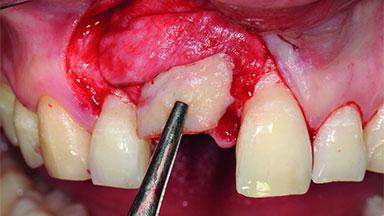

Replacement of a Compromised Upper Right Central Incisor: Hard- and Soft-tissue Augmentation, Late Placement of an RC Bone Level Implant

A 36-year-old male patient with a compromised maxillary central incisor was referred by his general dentist for consultation. The patient’s chief complaints were the gradual debonding of a temporary crown on the right central incisor and unsatisfactory esthetics due to an increasing diastema between the right central and lateral incisors. The patient reported a traumatic event some years previously, when a crown had been placed after root-canal treatment. The referring dentist wanted to provide a new crown restoration, but was concerned about the condition of the residual root. Anamnesis was negative for any other dental or periodontal pathology in the remaining dentition. The patient reported taking no medications: He was a smoker (10 to 15 cigs/day) and had realistic esthetic expectations.

Bone Augmentation Horizontal|Simultaneous|Staged

Soft Tissue Grafting Simultaneous

Bone Volume Deficient horizontally, requiring prior grafting